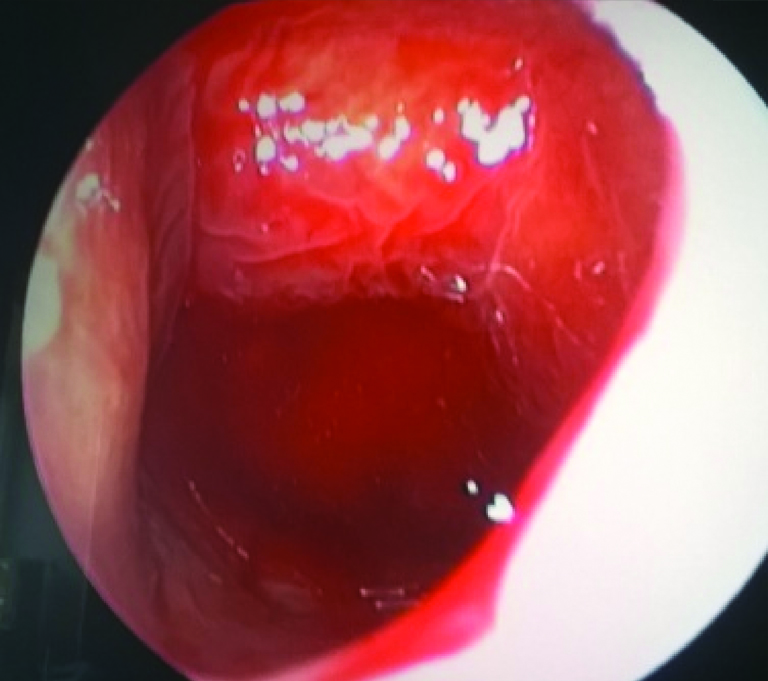

ВВЕДЕНИЕ В настоящее время в связи с распространением лучевых (МРТ, КТ) и визуальных (эндоскопия) методов диагностики наблюдается увеличение количества случаев изолированного сфеноидита [1, 2, 3]. Удельный вес изолированного сфеноидита в общей структуре заболеваний околоносовых пазух (ОНП), по данным литературы, составляет не более 5% [4, 5, 6]. Однако абсолютные цифры с учетом огромного количества случаев воспалительной патологии ОНП могут быть весьма значительными. В структуре синуситов все больше резистентных (устойчивых к лечению) форм, в том числе грибковых [7]. Данные о распространенности патологии весьма скудные, в структуре статистической отчетности стационаров и поликлиник сфеноидит как самостоятельная нозологическая форма отражается крайне редко. В то же время относительно невысокая распространенность нередко обусловливает пассивную позицию специалистов при дифференциальной диагностике поражений клиновидной пазухи (КП). Основное место в дифференциальной диагностике у данной группы пациентов занимают компьютерная томография (КТ) и магнитно-резонансная томография (МРТ). Однако трактовка результатов исследований не всегда однозначна и может приводить как к гипердиагностике, так и, наоборот, к гиподиагностике сфеноидита, выражающейся в недооценке данных лучевой диагностики и обьективной картины и нередко приводящей к развитию хронических и осложненных форм. Пациенты направляются к лор-врачу только после длительного, безуспешного лечения у специалистов смежных специальностей, что влечет высокий уровень гиподиагностики сфеноидита и наличие осложненных форм [8]. Дифференциальная диагностика патологического процесса в пазухе на дооперационном этапе чрезвычайно важна, поскольку необдуманное вмешательство может вызвать тяжелые и даже фатальные осложнения [9, 10]. От 5% до 30% всех изолированных поражений клиновидной пазухи составляют пациенты с неинвазивной грибковой формой [11, 12]. Для хронического сфеноидита характерно латентное (скрытое) течение, которое не всегда диагностируется на ранних стадиях [13, 14]. По данным ряда исследователей, частота патологических находок в клиновидной пазухе при аутопсии лиц, прижизненный диагноз «сфеноидит» у которых не был установлен, составляет от 10% до 68% [15, 16]. Очень важно изучение вопросов ремоделирования в клиновидной пазухе, в том числе явлений остеита при грибковых формах [17]. Осложненное течение изолированного сфеноиди-та - нередкое явление, при этом основным фактором развития осложнений является несвоевременная диагностика. Наиболее часто встречаются осложнения, связанные с вовлечением в патологический процесс глазодвигательных нервов, в особенности VI пары - n. abducens [4, 9, 16]. В литературе можно встретить наблюдения инвазивных, генерализованных форм грибкового сфеноидита с быстрым развитием офтальмологических, интракраниальных и системных (септических) осложнений [7, 12, 14]. Тактика лечения при изолированных поражениях клиновидной пазухи, по данным литературы, различная. Часть авторов считает наличие изолированного сфеноидита, особенно грибковых форм, мукоцеле, абсолютным показанием к операции. Другие авторы при отсутствии осложнений начинают с консервативной терапии [1, 3, 11, 12]. Задачей хирургического лечения у таких пациентов является не только купирование воспалительного процесса, но и создание условий для адекватной вентиляции пазух и предотвращения возможного рецидива. В то же время вопросы дифференцированного подхода к хирургическому лечению недостаточно освещены в научной литературе и носят преимущественно описательный характер. ш ЦЕЛЬ Провести анализ случаев изолированного поражения клиновидной пазух и выявить основные особенности и ошибки при дифференциальной диагностике на догоспитальном этапе. ш МАТЕРИАЛ И МЕТОДЫ В работе приведены данные о лечении 58 пациентов с изолированным поражением клиновидной пазухи, которые находились на стационарном лечении в ГБУЗ НОКБ им. Н.А. Семашко (кафедра болезней уха, горла и носа ФГБОУ ВО «ПИМУ» Минздрава РФ) в период 2015-2018 гг. Возраст пациентов - от 18 до 68 лет. Средний возраст пациентов с изолированным сфеноидитом составил 43 года, среди них превалировали женщины до 35 лет. Гендерное распределение было следующее: мужчины - 21 (30,7 %), женщины - 37 (69,3%). Давность заболевания составила 26±19 дней. Всего в клинике в данный период наблюдались 118 пациентов с различными формами поражения клиновидной пазухи, у 60 пациентов поражение КП наблюдалось как проявление хронического риносинусита (с полипами и без), то есть имело место сочетанное поражение нескольких или всех околоносовых пазух, и данные наблюдения не были включены в исследование. Критерии включения в исследование: рентгенологические (КТ, МРТ) признаки патологического процесса в клиновидной пазухе, специфическая и неспецифическая симптоматика, латентное течение сфеноидита, отсутствие патологического процесса в других околоносовых пазухах. Критерии исключения: сочетанное поражение других групп околоносовых пазух, нозокомиальный сфенои-дит. Такие состояния, как искривление носовой перегородки, вазомоторный/аллергический ринит, гипертрофия носовых раковин, mnchabullosa средних носовых раковин критериями исключения не являлись. Пациенты с впервые установленным диагнозом составили 85% от общего числа, 15% наблюдений - рецидивные формы заболевания, в том числе 5 пациентов были после ранее проведенного оперативного вмешательства (таблица 1). Морфологическая форма Количество наблюдений Полипозный процесс 15 (25,8%) Киста 18 (31%) Мукоцеле 5 (8,6%) Грибковый сфеноидит 12 (20,6%) Инвазивный грибковый сфеноидит 2 (3,4%) Менингоцеле 4 (6,8%) Новообразование 2 (3,4%) Таблица1. Распределение по виду патологического процесса Table 1. Distribution by the type of pathological process При поступлении в стационар проведено обследование пациентов в следующем объеме: клинические анализы, консультации смежных специалистов - невролога, нейрохирурга, офтальмолога (в зависимости от клинических проявлений). Всем пациентам проводилась предоперационная эндориноскопия. При подготовке к оперативному лечению оценивалось наличие у пациента сопутствующих заболеваний, течение которых проявляется симптоматикой со стороны ОНП и может в значительной степени оказывать влияние на течение патологического процесса в полости носа и ОНП: бронхиальная астма, аспириновая триада, персистирующий или интермиттирующий аллергический ринит, а также комбинация данных заболеваний. ш ОБСУЖДЕНИЕ И РЕЗУЛЬТАТЫ В большинстве случаев причиной обращения за помощью был цефалгический синдром. Все пациенты с болевым синдромом первоначально проходили обследование у невролога либо терапевта, им выполнялось МРТ-исследование на догоспитальном этапе. В данной группе пациентов (n=21, 36,2%) 9 человек были направлены к оториноларингологу сразу после получения данных МРТ. 12 пациентов проходили дальнейшее консервативное лечение у невролога либо не получали никакого лечения, несмотря на очевидные данные МРТ-исследования. После МРТ-исследования уточняющее КТ-исследование было назначено только 3 пациентам. Остальные пациенты были направлены в стационар с результатами МРТ. Таким образом, в рамках нашего исследования можно говорить о превалировании МРТ-диагностики в догоспитальном обследовании и игнорировании специалистами КТ-исследования. Симптоматическая картина у исследуемых пациентов весьма вариабельна: от латентных бессимптомных форм до тяжелых цефалгических и офтальмологических проявлений. Мы наблюдали определенную взаимосвязь между симптоматическими проявлениями и морфологической формой заболевания (таблица 2). В целом манифестирующая ринологическая симптоматика наблюдалась не более чем в трети наблюдений. В остальных ситуациях мы наблюдали либо неспецифическую симптоматику (цефалгические и/ или офтальмоплегические проявления), либо бессимптомное течение. Латентные формы поражений КП, когда патологический процесс выявлен случайно при МРТ/КТ-обследовании по другим причинам, составили около 20% от всех наблюдений. Чаще всего это были поражения в виде кисты клиновидной пазухи и мукоцеле (рисунок 1), реже бессимптомное течение наблюдалось при грибковой форме поражения и менингоцеле (рисунки 2, 3). Хирургическое лечение. Всем пациентам проводилось хирургическое лечение, после тщательного анализа КТ-томограмм для уточнения варианта строения клиновидной пазухи и наличия анатомических вариантов строения (клетки Оноди, дигисценции канала внутренней сонной артерии, зрительного нерва и т.д.) (рисунки 4а, 4б). Все оперативные вмешательства выполнялись под общим обезболиванием. Применялись следующие доступы: трансназальный, расширенный трансназальный, трансэтмоидальный, доступ по методике Bolger Box, транскрыловидный (в одном случае) (таблица 3, фото 5, 6). Расширенный доступ (Wormald PJ. 2005, Palmer J.N. 2013) в отличие от традиционного с механическим расширением естественного соустья подразумевает выкраивание короткого (5-10 мм) назосептального лоскута Морфологическая форма Клинические симптомы Головная боль Постназальный затек Голово кружение Назальная обструкция Глазничные симптомы Полипозный процесс/ полипозно-гнойный + +++ - ++ - Киста - - - + - Мукоцеле ++ + - + - Грибковый сфеноидит ++ ++ + + + Инвазивный грибковый сфеноидит +++ ++ + + +++ Менингоцеле + + + - - Новообразование ++ + + - +++ «+» - степень выраженности симптома от + до +++. «-» - отсутствие симптома. Таблица 2. Симптоматические проявления Table 2. The symptomatic manifestation Рисунок 1. Мукоцеле клиновидной пазухи. Figure 1. Mucocele of the sphenoid sinus. Рисунок 2. Грибковый сфеноидит. 2.1 КТ (аксиальный срез); 2.2 Соустье обтурировано полипом. Трансназальный доступ; 2.3 - грибковые массы в пазухе. Figure 2. Fungal sphenoiditis. 2.1 CT (axial cross-section); 2.2 Anastomosis is obturated by a polyp. Transnasal access; 2.3 - fungal masses in the sinus. Рисунок 3. КТ (фронтальный срез). Остеит стенок клиновидной пазухи при грибковом синусите. Figure 3. CT (front section). Osteitis of the walls of the sphenoid sinus in fungal sinusitis. Рисунок 4а. Дигисценция канала внутренней сонной артерии. КТ-исследование. Figure 4a. Dehiscence of the internal carotid artery channel. CT study Рисунок 4б. Дигисценция канала внутренней сонной артерии. Эндоскопическая картина. Figure 4b. Dehiscence of the internal carotid artery channel. Endoscopic image. Таблица 3. Виды хирургических вмешательств Table 3. Types of surgical interventions слизистои ниже и медиальнее соустья пазухи на ножке с питанием от заднеИ септальноИ ветви крылонебной артерии с широким обнажением и резекцией передней стенки пазухи. При этом соустье мы расширяли при помощи бора. Данный способ упрощает задачу в том случае, если естественное соустье не визуализируется и технически не доступно и/или есть необходимость широкого открытия пазухи. Лоскут на питающей ножке используется для закрытия широкого костного дефекта, что способствует его дальнейшей эпите-лизации и минимизирует развитие в последующем остеита. Исследования ряда авторов свидетельствуют о том, что трансэтмоидальный и трансназальный доступ могут с одинаковым успехом применяться при Рисунок 5. 5a - грибковое тело латерального кармана клиновидной пазухи (КТ, аксиальный срез); 5b - расширенный трансназальный доступ (700 эндоскоп); 5c - КТ через 6 мес. после операции. Figure 5. 5a - fungal ball in the lateral “pocket" of the sphenoid sinus (CT, axial section); 5b - extended transnasal access (700 endoscope); 5c - CT in 6 months after operation. Рисунок 6. Менингоцеле клиновидной пазухи. 6а - МРТ (фронтальный срез); 6b - расширенный трансназальный доступ. Пластика ликворного дефекта после удаления менингоцеле (материал - жир). Figure 6. Meningocele of the sphenoid sinus. 6a - MRI (frontal section); 6b - extended transnasal access. Plasty of the liquor defect after the meningocele removal (the material - fat). Рисунок 7. Соустье через 1 год после расширенного доступа. Figure 7. Anastomosis 1 year after expanded access. Рисунок 8. Соустье через 3 года после расширенного трансназального доступа. Рисунок 9. Рецидив полипозно-гнойного сфеноидита через 6 месяцев после операции. причиной рецидива патологического процесса и потребовал проведения ревизионного вмешательства. В одном случае у пациента, которому ранее выполнена сфенотомия по поводу хронического сфеноидита, но не была вскрыта (распознана) клетка Оноди, в которой локализовалось грибковое воспаление, также потребовалась повторная операция. Figure 9. Recurrence of polypous-purulent sphenoiditis in 6 months after surgery. Figure 8. Anastomosis 3 years after expanded access. изолированном поражении пазухи. Трансназальный доступ более безопасен, чем трансэтмоидальный, и является методом выбора при изолированном поражении пазухи при условии, что патологический процесс в пазухе не требует широкой ревизии и/или создания достаточного по объему сообщения в тех ситуациях, когда велик риск рецидива. Осложнений в послеоперационном периоде не наблюдалось. На 5-7 сутки всем пациентам выполнялась эндориноскопия. В срок от 2 до 3 месяцев 11 пациентам выполнено контрольное КТ. Остальные пациенты (из отдаленных районов) не проходили контрольного осмотра. При выполнении расширенного доступа удалось добиться формирования стойкого, эпителизи-рованного соустья во всех случаях (рисунки 7, 8). При полипозно-гнойных формах сфеноидита наиболее часто наблюдались рецидивы заболевания, однако здесь требовалась только противовоспалительная терапия, в том числе орошение пазухи через сформированное соустье (рисунок 9). Частота развития спаечного процесса после вмешательств составила около 20%, при этом только в 3 наблюдениях рубцово-спаечный процесс явился ш ВЫВОДЫ Изолированный сфенои-дит в структуре пациентов, которым проводилось эндохирургическое лечение при патологии ОНП, составил 3% (около 30% от общего числа сфеноидитов). В стационаре пациенты с точно установленным диагнозом «изолированный сфеноидит» на догоспитальном этапе составили не более 12% от общего числа, что связано как с гиподиагностикой, пассивной позицией в отношении патологии клиновидной пазухи у врачей амбулаторного звена, так и с тактическими ошибками. Отмечено превалирование МРТ-диагностики в догоспитальном обследовании и игнорирование специалистами КТ-исследования. Основной метод лечения изолированного сфеноидита - хирургический. Наиболее часто применялся расширенный трансназальный доступ. Необходимо сочетание с медикаментозным лечением в послеоперационном периоде. Требуются дальнейшие исследования с целью изучения особенности/безопасности и клинической эффективности различных эндохирургических доступов. W Конфликт интересов: все авторы заявляют об отсутствии конфликта интересов, требующего раскрытия в данной статье.Об авторах